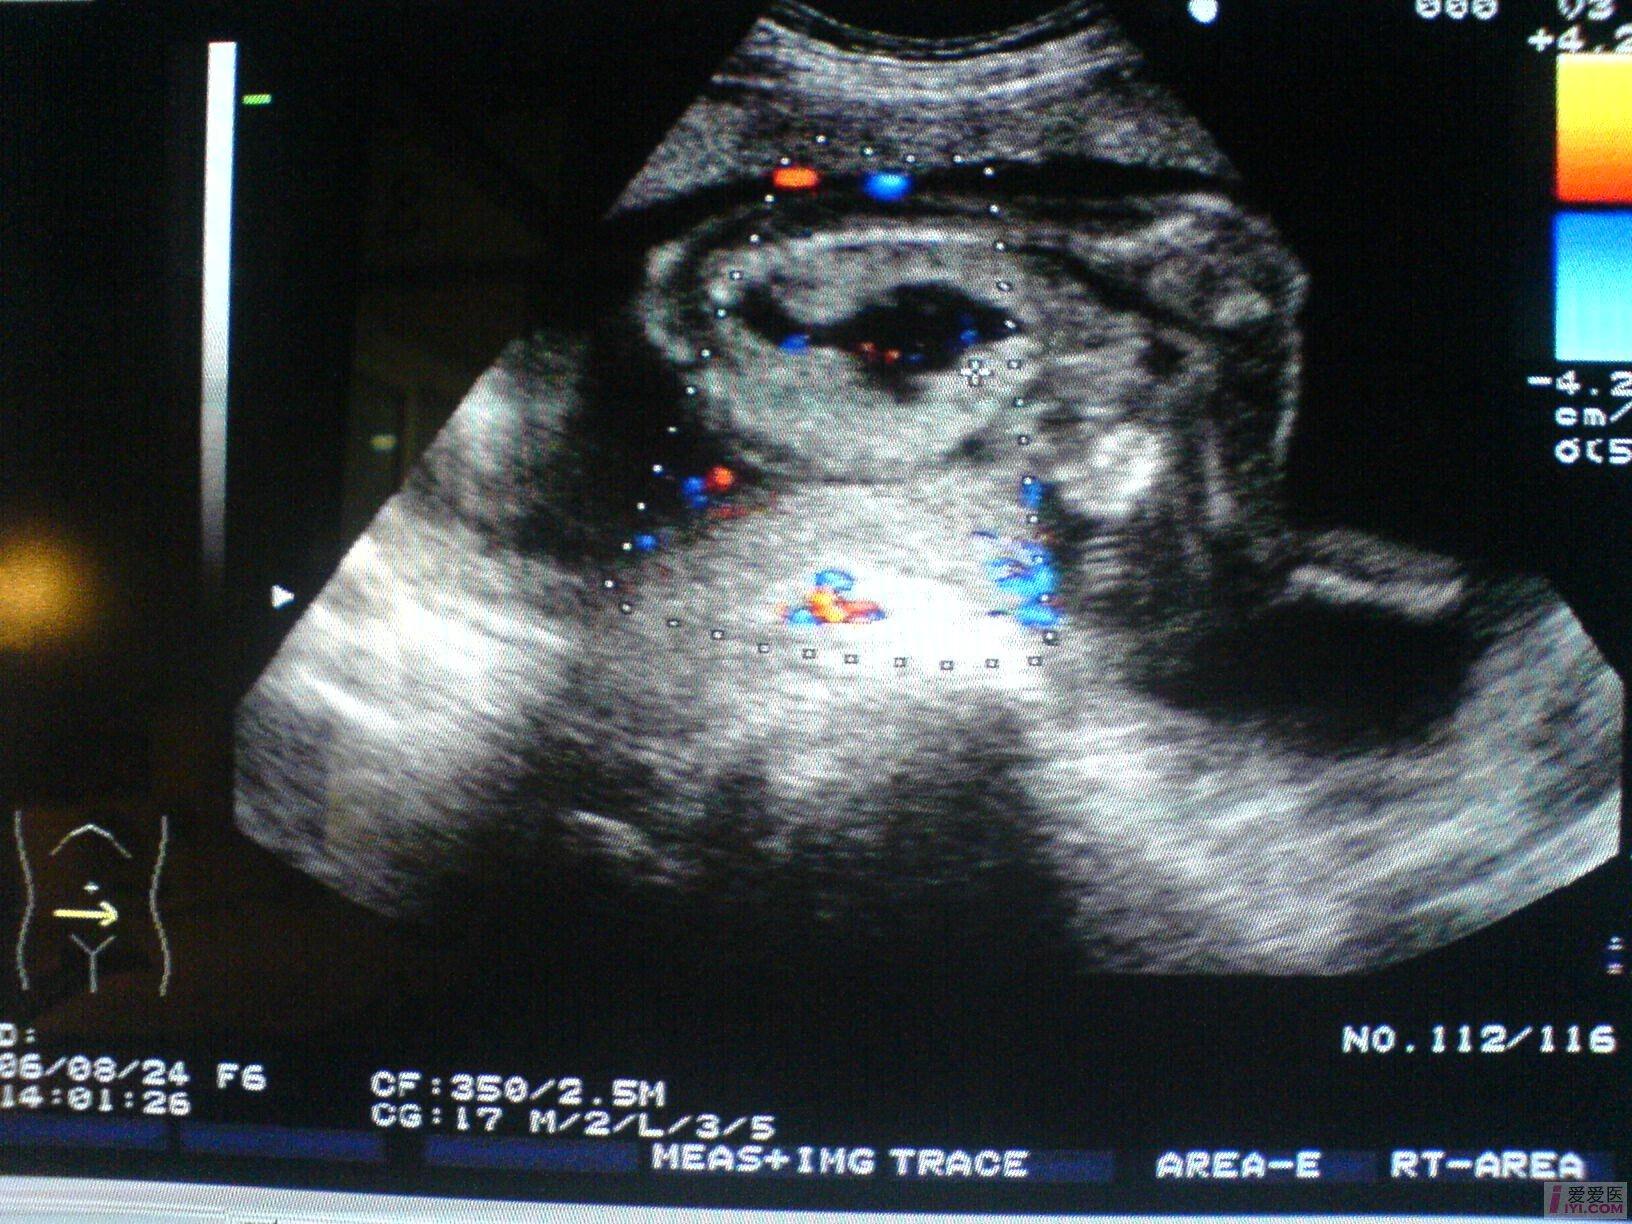

B超所见:宫内单胎妊娠,胎头双顶径51mm,股骨长35mm,胎儿脊柱完整,肺实质回声增强,右侧肺叶内见31X18X17mm不规则无回声区,边界清晰,内透声好,CDFI:无回声区内未见血流信号。胎儿心胸比例失常,心脏明显受压,胎儿肝脏增大,位置下移,占据整个腹腔,回声增粗,欠均匀,未见胃泡回声,肝脏周围见宽4mm无回声暗区。胎动活跃,胎心搏动好,胎心律150bpm,胎盘附于前壁,厚21mm,回声均匀,最大羊水暗区深度74mm,透声好。

2.胎儿肺实质回声增强,右侧肺叶囊性占位,肝大,少量腹水。

胎儿先天性肺囊腺瘤注意和先天性膈疝、隔离肺、神经源性肿块、食管重复畸形等形成的肿块相鉴别,通常如果肿块类似实性时,则应考虑微囊型先天性肺囊腺瘤畸形和隔离肺。而神经源性肿块、食管重复畸形的肿块主要位于后纵隔。动态观察隔离肺,大部分(50%~70%)隔离肺随孕周的增加而部分或完全萎缩。包块滋养血管来自胸主动脉或腹主动脉,CDFI检出此种声像特征可以帮助区分隔离肺与其他肺肿块(如先天性肺囊腺瘤、肺泡性肺气肿、支气管闭锁等)。后者的滋养血管均来自肺动脉。 虫虫3代战友,这题可不好答:关于胎儿先天性肺囊腺瘤样畸形的描述,下面哪一项不正确( ) A. 是胎儿肺部恶性肿瘤 (错。先天性肺囊腺瘤畸形是一种肺组织错构畸形。) B. 多为双侧(错。先天性肺囊腺瘤畸形典型者为单侧,可累及一侧肺或一叶肺,但是95%以上仅限于一叶或一段肺。) C. 囊泡小于5mm预后较好 D. 囊泡大于20mm预后较差(目前认为肿块大小、纵隔移位程度、是否出现胎儿水肿和羊水过多,均与预后好坏有关,是判断预后的重要指标。出现胎儿水肿者,预后最差,有学者报道其死亡率高达100%。) E. 可在出生前消失 (据报道,约70%的先天性肺囊腺瘤畸形病例,肿块大小较稳定;约20%产前明显萎缩或消失;仅10%是进行性增大。在有症状的新生儿中,手术后生存率达90%,而无症状的新生儿是否需要手术治疗尚不肯定。)